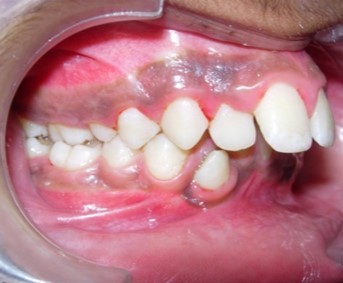

Intraoral assessment. (Figure 1d,Figure 1e,Figure 1f,Figure 1g,Figure 1h).

Figure 1e.Pre-treatment intra-oral-Right

The maxillary arch was V-shaped with severely proclined and rotated maxillary incisors with a palatally placed 12. The mandibular arch was U-shaped with severe crowding of mandibular incisors, with 43 partially erupted and buccally placed with transpositioned 42 and 43, with 42 mesiolingually rotated, 33 distolingually rotated and 34 distolingually rotated and buccally placed.

Severe increase in overjet and deep bite were both observed. The maxillary midline coincided with the skeletal midline but the mandibular midline was shifted to the right side by 1 mm. Bilateral maxillary posterior crossbite was also observed. On right side the molar relation was Class I and on the left side it was Class II. The canine relation was Class II on the left side and the curve of Spee was increased.